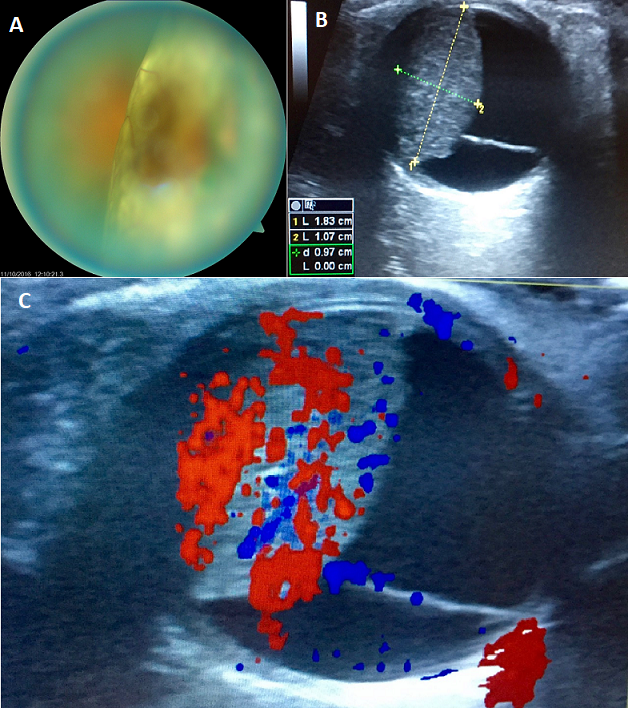

Nous rapportons le cas d'une patiente de 56 ans, sans antécédents pathologiques notables, ayant consulté aux urgences pour une baisse de l'acuité visuelle de l'œil droit, installée depuis 2 semaines. A l'examen ophtalmologique, on trouve une acuité visuelle réduite au mouvement de doigts, avec au fond d'œil un décollement de rétine séreux associé à une masse sous rétinienne comblant une majeure partie de la cavité vitréenne (A). Une échographie oculaire en mode B a été réalisée et a mis en évidence une masse choroïdienne isoéchogène (B) vascularisée prenant le doppler (C) sans excavation, mesurant 18 mm de grand axe associée un décollement séreux de la rétine, fortement évocatrice d'une métastase oculaire. Un bilan général a été réalisé et notamment une mammographie qui a révélé l'existence d'un nodule du sein droit stade 4 selon la classification BI RADS. Une Tomodensitométrie thoraco abdomino pelvienne, et cérébrale dans le cadre du bilan d'extension a montré la présence de nombreuses métastases cérébrale, osseuse et hépatique. Le diagnostic de cancer du sein métastatique a donc été posé, et la patiente a été référé en Oncologie pour prise en charge spécialisée. Les métastases oculaires sont les tumeurs intraoculaires les plus fréquentes. Les carcinomes mammaires représentent la principale cause des métastases choroïdiennes, justifiant un bilan exhaustif lors de la mise en évidence de ces tumeurs intra oculaires.